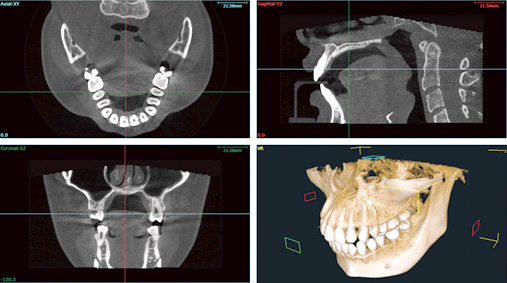

私たちが、最新のCT機器を用いることで、mm単位で神経との距離を把握でき、歯の神経を出来るだけ残す治療を心がけているからです。

さらに、CTに加えて、セファロや光学3Dスキャナー等の最新機器を組み合わせることで、歯を削る量をmm単位で調整することができ、削る量を最小限におさえて、痛みや見た目だけでなく、数十年先までの歯の健康、寿命までも考えた"歯に優しい虫歯治療"を追求しているからです。

問診・CTスキャンの撮影 歯・口元に関する悩み、理想とする状態などをヒアリングした上で、歯の状況や神経の場所などを詳細に診断します。 |

初回検査・初回集中治療 当日又は後日、初回検査を行います。CT、セファロ検査、レントゲン等の検査を行い、詳細な治療計画を決定します。 カウンセリングを受けた後、すぐに決める必要はありません。ちょっとでも迷うようであれば、お家に帰ってよく検討してみてください。家族や友人に相談するのも良いと思います。 |